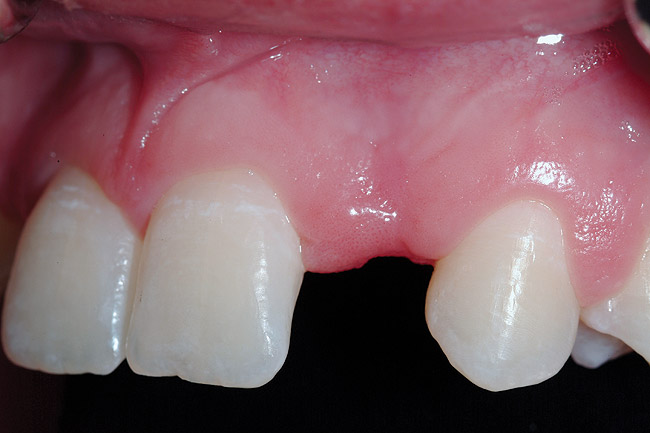

Figure 5  Pretreatment clinical view, left lateral incisor.

Figure 5

A 19-year-old non-smoking female presented for tooth replacement at the maxillary right and left lateral incisors, which were congenitally missing (Figure 1). The post-orthodontic result was adequate for the placement of 3-mm one-piece small-diameter implants. The preoperative radiographs can be seen in Figure 2 and Figure 3. The pretreatment clinical view in Figure 4 and Figure 5 shows the small intertooth space present in the lateral incisor areas. One of the most challenging tasks with congenitally missing lateral incisor cases is to create an acceptable soft tissue emergence profile from a crestal profile that is flat from the mesial of the canines to the distal of the centrals (Figure 4 and Figure 5). After pretreatment planning which consisted of a complete medical and dental history, radiographic analysis, and upper and lower study models mounted by a facebow transfer technique, the fabrication of a TempStent II surgical guide was completed. Figure 6 and Figure 7 show the occlusal view of the TempStent II guide on the study cast and in the oral cavity, respectively.